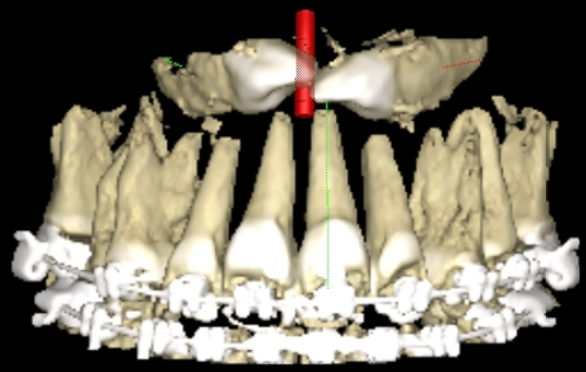

Endodontic Treatment: Challenges and Difficulties of Access Cavities -- Case Series

El Kharroubi Soukaina, Dhoum Sara, Doumari Bouchra, Drouri Sofia, Laslami Kaoutar and El Ouazzani Amal. 22(6): 38-47.